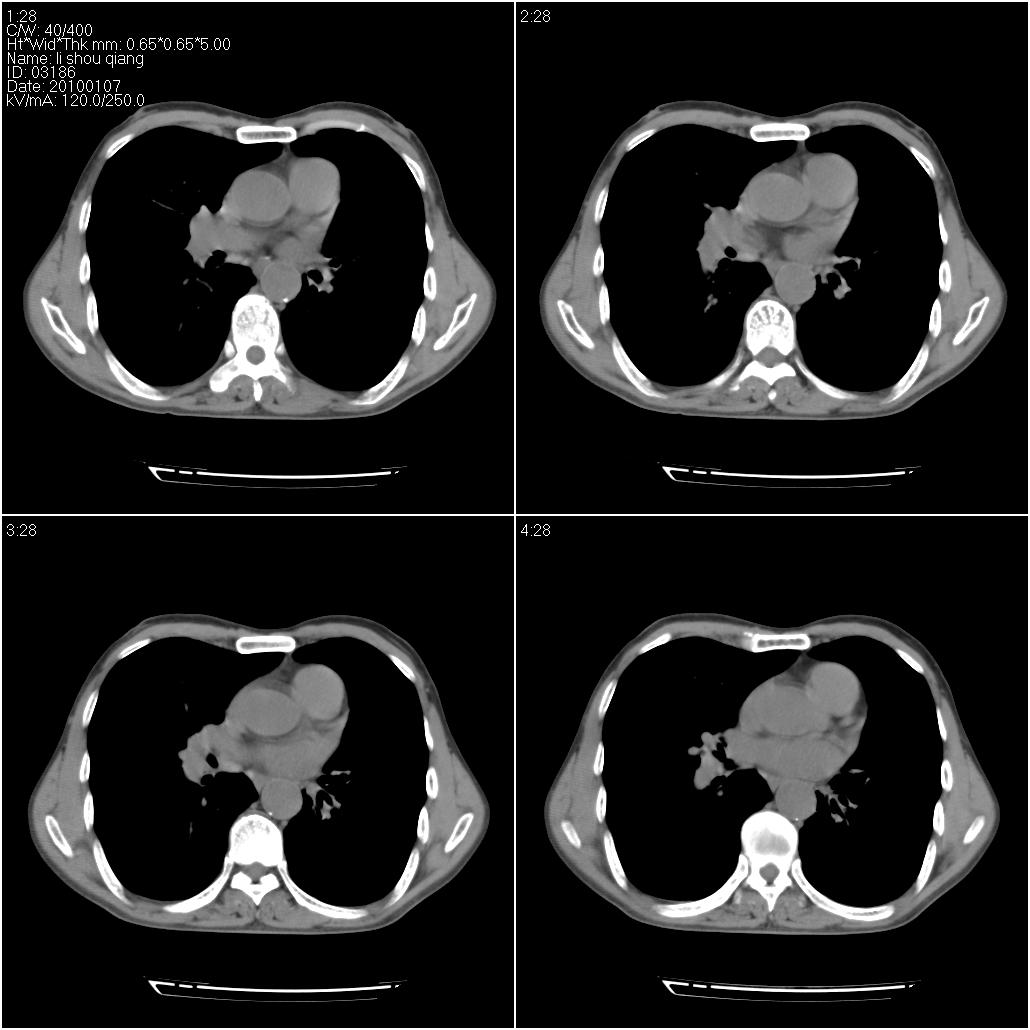

标题: CT24038:男性,58岁。主因咳嗽带血性CT检查。 [打印本页]

标题: CT24038:男性,58岁。主因咳嗽带血性CT检查。

3、建议增强除外主动脉弓息室样动脉瘤。

右肺中叶外侧段可见团块影,外形不规则,内见空泡征。左下肺见蜂窝状低密度透亮影,部分层面主动脉旁瘤样突出。考虑右肺中叶外围型肺癌可能性大,左下肺支气管扩张,主动脉弓瘤样突出。

考虑右肺癌可能性大,左下肺支气管扩张,主动脉弓瘤样突出?建议增强

3、建议冠状位重建除外主动脉弓息室样动脉瘤。